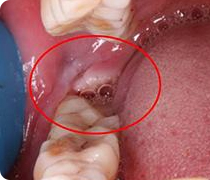

检查拍片

微创器械拔牙

创口小出血少

术后反应轻